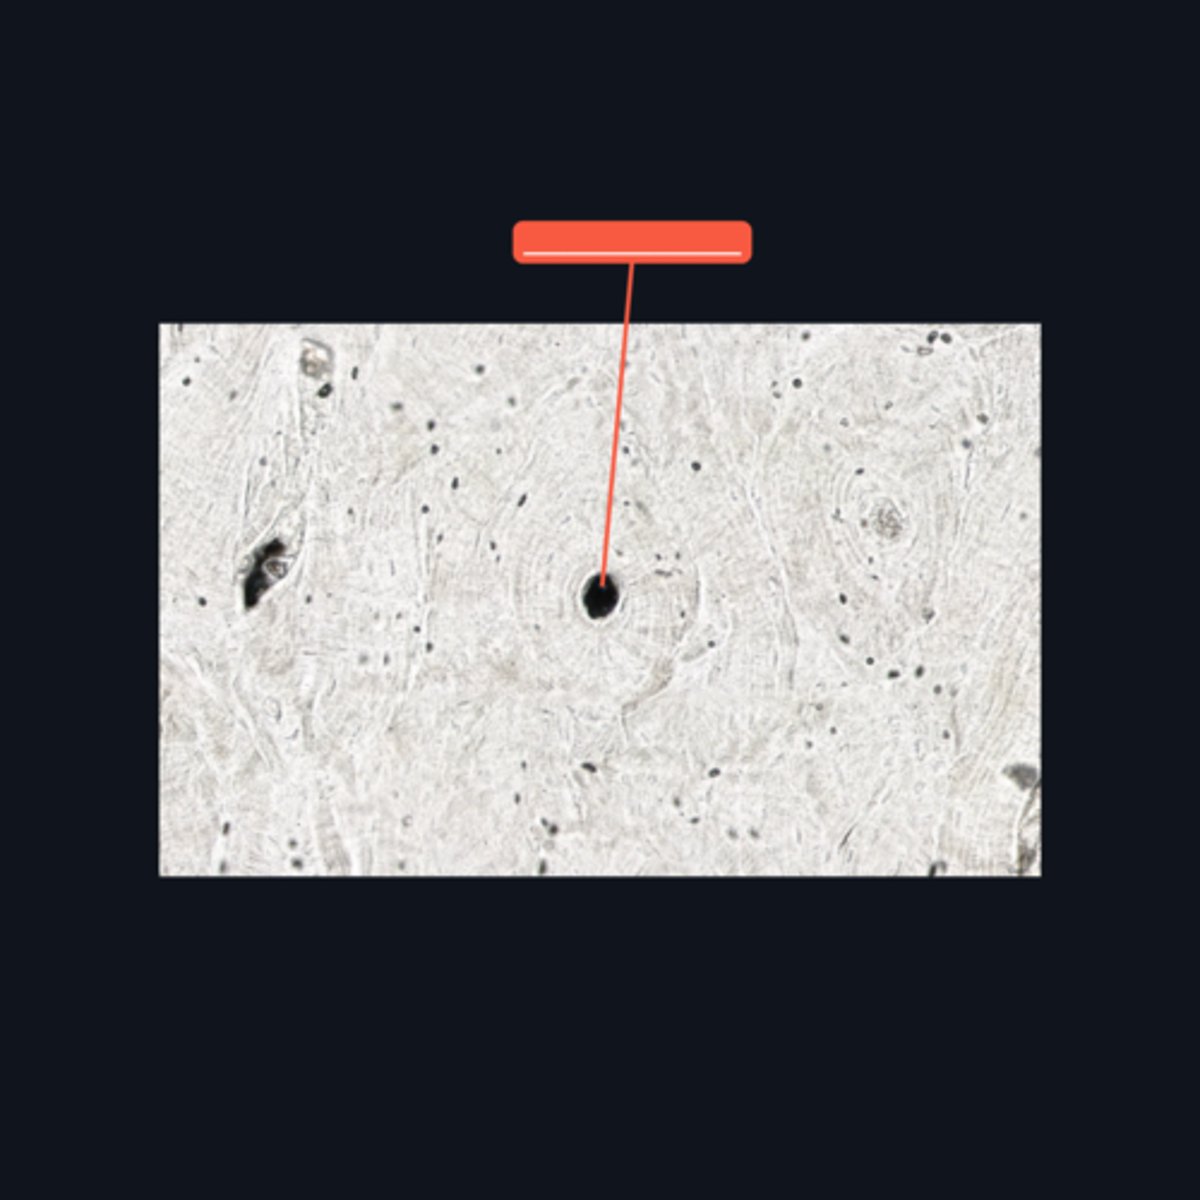

Fibrocartilage; intervertebral disc, articular disc, glenoid and acetabular labra

What type of cartilage is in the image? Where is this specific type of cartilage found?

Collagen fibers

This type of cartilage is abundant in what fibers?

Dense regular connective tissue; chondrocytes; lacunae

This cartilage is commonly mistaken as _____. However, when examined closely, _____are contained in _____ (identify pointed structures), making it a cartilage.